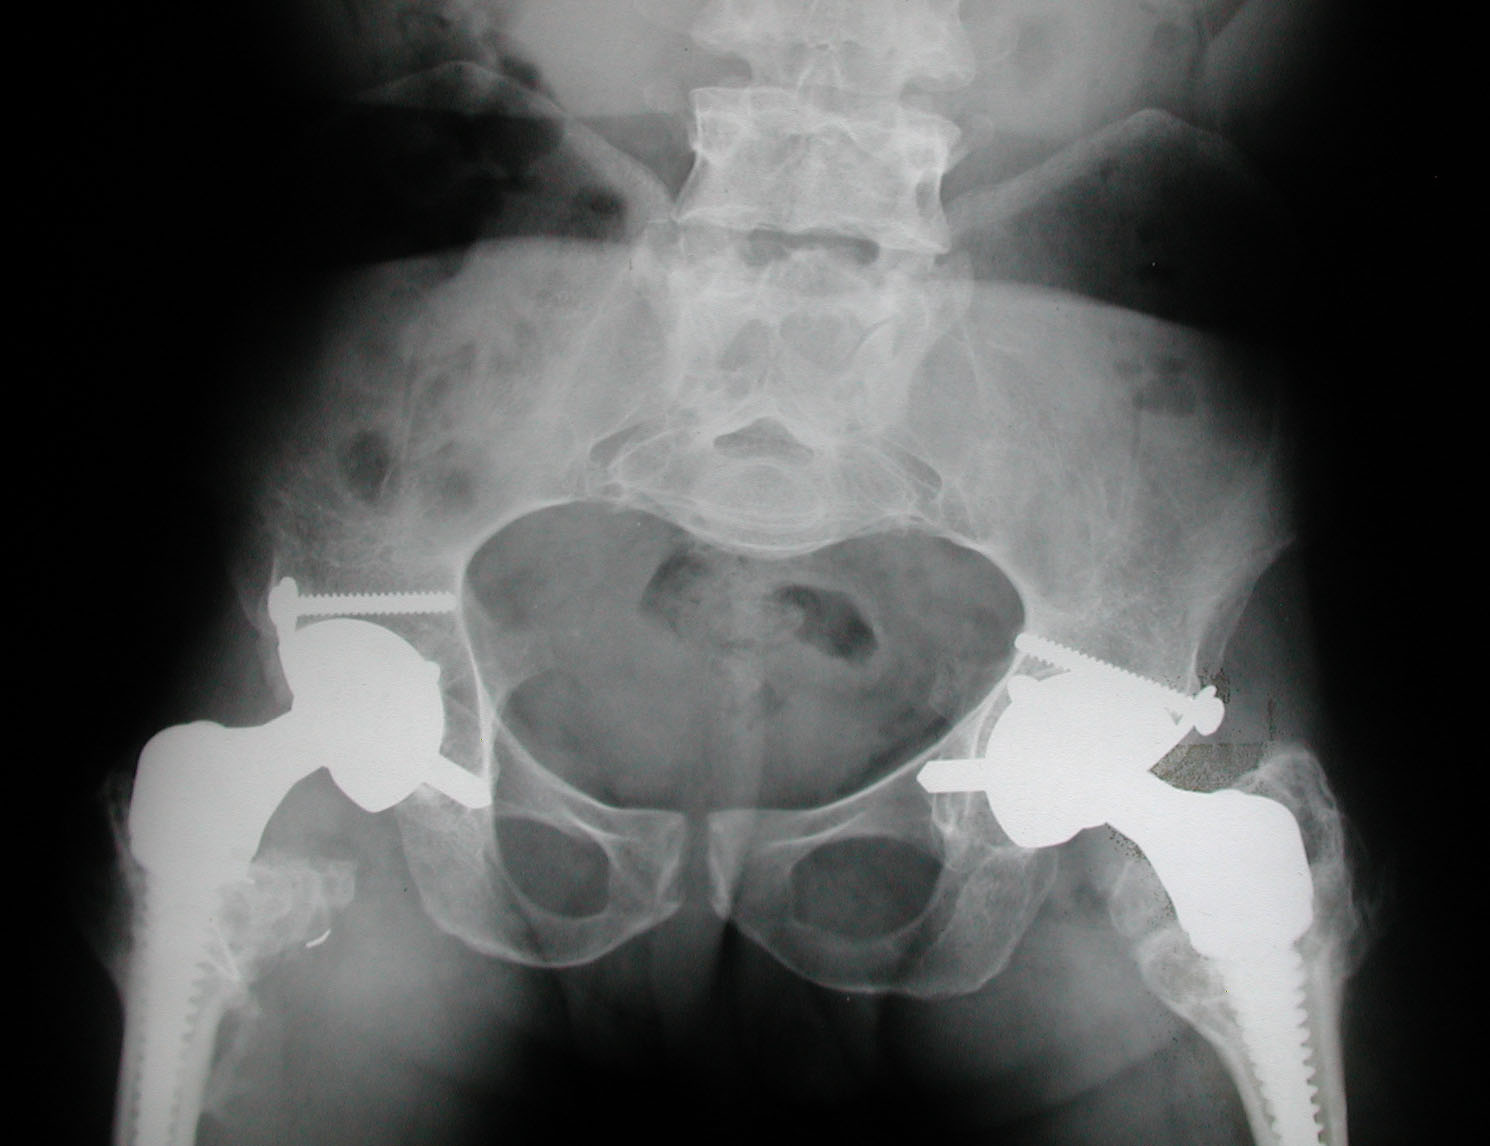

7. Sekundiak TD. Total hip arthroplasty in patients with dwarfism. Orthopedics 2005;28(9):1075-8.

8. Huo MH, Salvati EA, Liberman JR, Burstein AH, Wilson PD Jr. Custom-designed femoral prostheses in total hip arthroplasty

done with cement for severe dysplasia of the hip. J Bone Joint Surg Am 1993;75:1497-1504.

9. Osagie L, Figgie M, Bostrom M. Custom total hip arthroplasty in skeletal dysplasia. International Orthopedic 2012;36:527-1.

10. Chiavetta JB, Parvizi J, Shaughnessy WJ, Cabanela ME. Total hip arthroplasty in patients with dwarfism. J Bone Joint Surg

Am 2004;86:298-303.

11. Ain MC, Andres BM, Somel DS, Fishkin Z, Frassica FJ. Total hip arthroplasty in skeletal dysplasias. Patients selection,

preoperative planning, and operative techniques. J Arthroplasty 2004;19(1):1-7.